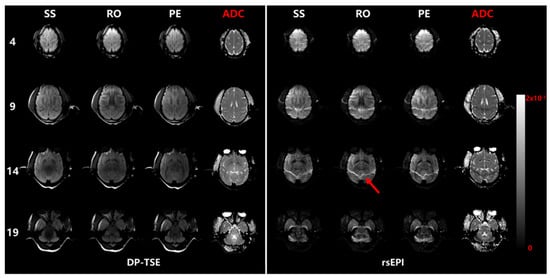

The raw diffusion images from orthogonal directions and ADC maps from two sequences with b = 1000 s/mm2 are selectively displayed in Figure 3. The images from DP-TSE reveal higher definitions of tissue texture, and provide more details to tell the specific distinctions in different diffusion directions than those from DW-rsEPI, indicating that the TSE-based dMRI can greatly preserve authentic information while excluding blurring from phase- or distortion-correction in further post-processing. In addition to general brain shape distortion because of the EPI readout scheme, the DW-rsEPI results also suffered from artifacts from fat shifting (red arrow) caused by a wider bandwidth of the protocol setup in fat suppression.

Figure 3. Diffusion images along three directions and calculated ADC maps from two protocols with b = 1000 s/mm2. The forehead distortion caused by EPI readouts and the fat shifting artifacts (red arrow) are shown in rsEPI-based images.

In this study, we simply pushed the resolution to 1 mm in-plane and a 2 mm thickness to demonstrate the fair differences between EPI-based and TSE-based sequences without image correction at 3 T; promising results suggest that the TSE-based approach has promising potential in achieving submillimeter-scale resolution at 3 T or even higher field strengths of the MR system. Moreover, without disturbing effects from EPI, TSE-based dMRI could be expected to provide for more complex fiber geometries such as fiber crossings at the whole brain level. The results in Figure 3 and Figure 4 demonstrate that the implemented DP-TSE sequence is suitable for anesthetic macaque brain dMRI and is able to reveal the superiority of high image quality, especially with high b-values, which paves the way to submillimeter dMRI study in NHPs. In additional, features such as no repetition scans and a parallel imaging capability may incite more possibilities for further research.